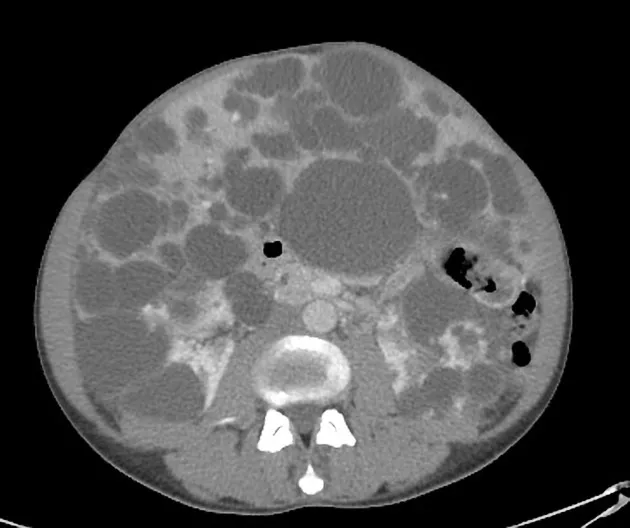

Diálise Peritoneal na Doença Renal Policística: existe algum motivo para não indicar?

A DRPAD não é contraindicação à DP — e, na prática, muitos pacientes têm resultados comparáveis à hemodiálise. O “porém” está na mecânica: rins/hepatomegalia podem reduzir tolerância a volumes, aumentar risco de hérnias e extravasamentos, e piorar desconforto respiratório. Com técnica adequada (cateter presternal ou lateral, volumes menores, cicladora noturna e decúbito supino), a maioria das barreiras é contornável. Neste post, revisamos quando a DP é ótima, quando exigir cautela e como ajustar a prescrição para segurança e qualidade de vida.